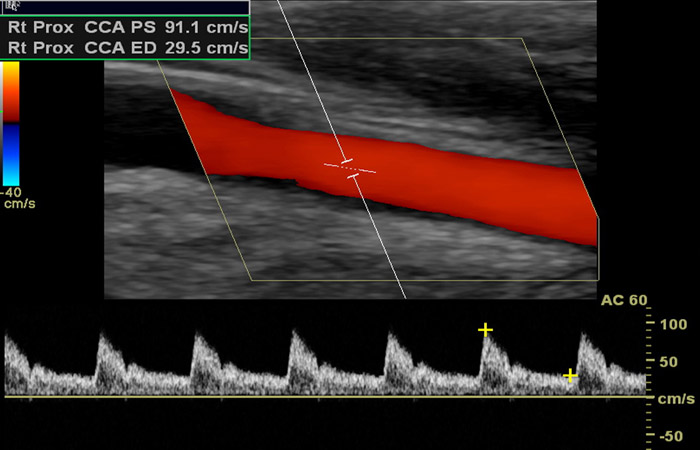

Το έγχρωμο Doppler υπερηχογράφημα ή triplex αγγείων είναι η μέθοδος με την οποία ελέγχουμε σε πραγματικό χρόνο την ροή του αίματος μέσα στα αγγεία του σώματος (π.χ. καρωτίδες, σπονδυλικές αρτηρίες, κοιλιακή αορτή, λαγόνιες αρτηρίες και φλέβες, φλέβες και οι αρτηρίες των άνω και κάτω άκρων) με τρόπο μη επεμβατικό, γρήγορο και ανώδυνο. Συγκεκριμένα, μας παρέχει πληροφορίες για την ανατομία των αγγείων, την τυχόν ύπαρξη αθηρωματικών πλακών ή στενώσεων στον αυλό των αρτηριών, την ύπαρξη και τον βαθμό επικινδυνότητας τυχόν ανευρύσματος της κοιλιακής αορτής, καθώς και για παθολογικές καταστάσεις των φλεβών ( θρόμβωση, βαλβιδική ανεπάρκεια).

Επίσης με τη χρήση του triplex είναι δυνατή η εκτίμηση της αγγείωσης του παρεγχύματος των διαφόρων οργάνων του σώματος, καθώς και η ανάδειξη της αιμάτωσης παθολογικών εξεργασιών.